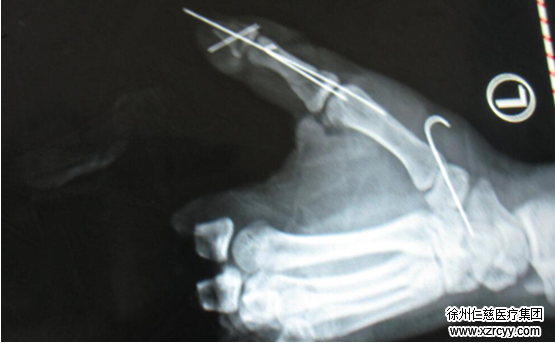

案例三:自制“土炸弹”左手四根手指被炸飞

年龄:14岁

伤情:左手2-5指离断,右环指中节指骨,其他手指也不同程度受伤。

与所有少年一样,小飞也是个贪玩爱闹的男孩。事发前,他与伙伴们正在自己家门口放鞭炮。不满足于一个个放的“无趣”,他决定尝试一个“新玩法”——将鞭炮中的火药拆开,倒进铁管——在敲击铁管的时候,意外发生了——药相互摩擦导致自燃,一瞬间,铁管在手中爆炸。小飞第一时间被家人送去当地医院治疗,因伤势过重,在简单包扎后被紧急送来医疗条件更好的徐州,于当天下午14:38抵达betway在线登陆。

因包扎伤创面污染较严重,无法行一期再造,1月24日的手术主要进行右手骨折复位内固定及清创标记断裂的血管神经肌腱断端,为二期手指再造进行相应的准备。待创面情况稳定进行皮瓣修复创面,创面愈合后予以脚趾移植手指再造。术后患者的左手功能将恢复原来的七八分。